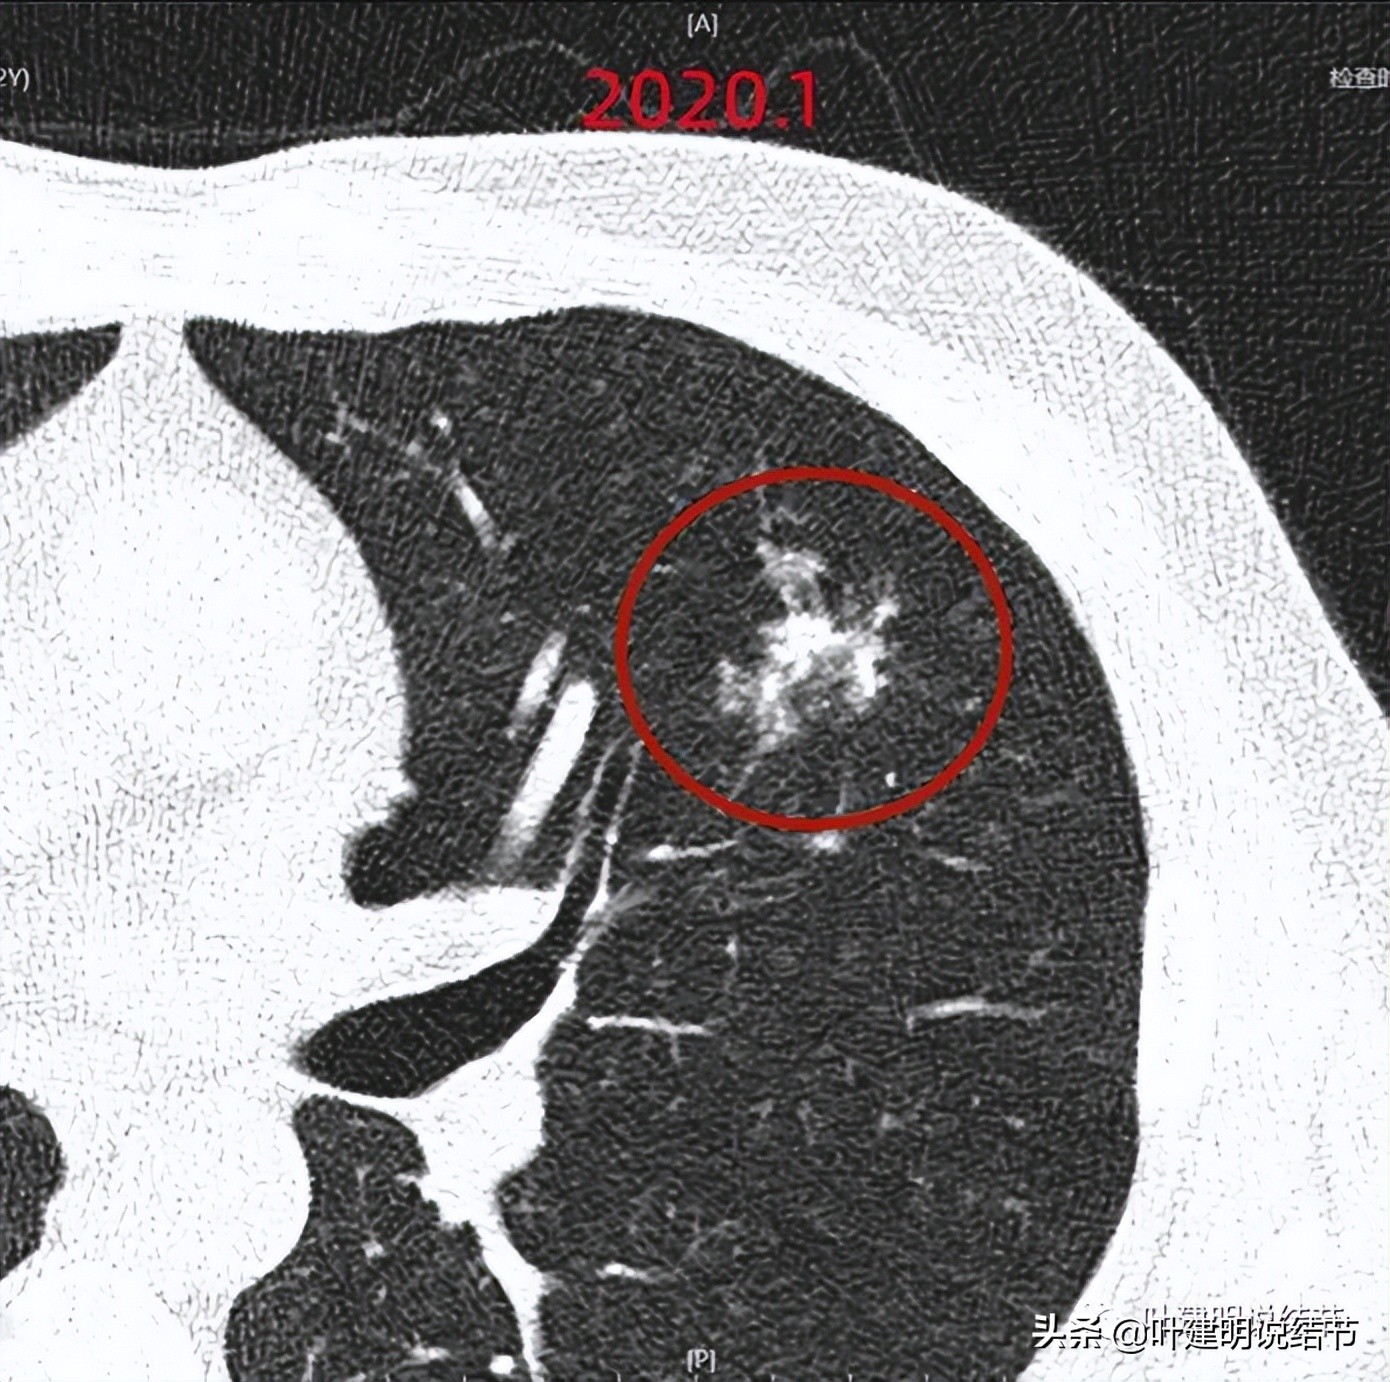

以上是2020年1月时的,病灶实性成分增多,较一年前有进展